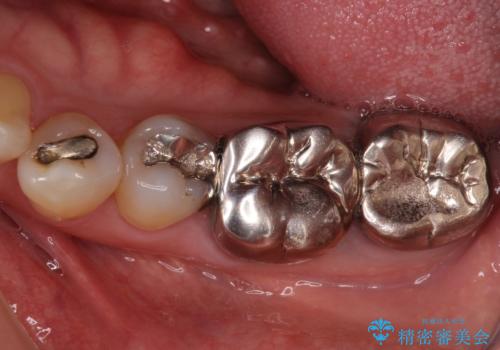

部分矯正期間中はアンカースクリューやフック、ゴムなどが粘膜にあたり、大変な思いをすることになりましたが、そのおかげでインプラント補綴した歯と最後方歯の位置が非常に良好となり、まるでご自身の歯のように咬むことができるようになりました。